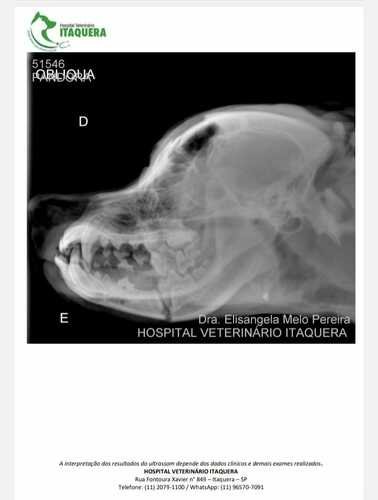

Oi, eu sou a Deise, dona da Pandora (cachorra acidentada) e estou aqui pedindo ajuda para arrecadar R$3.000,00 para realizar uma cirurgia de emergência na mandíbula devido a um acidente provocado por um atropelamento no dia 31 de março de 2024 (domingo de Páscoa). A cirurgia é de extrema emergência, pois a Pandora não consegue comer nem beber água, pois está com a boca extremamente quebrada. Já levei em vários veterinários públicos, mas os mesmos não realizam esse tipo de cirurgia, somente no particular, e o mais em conta que consegui foi R$3.000,00. Não tenho condições de arcar com esse valor, por isso peço a ajuda de todos.